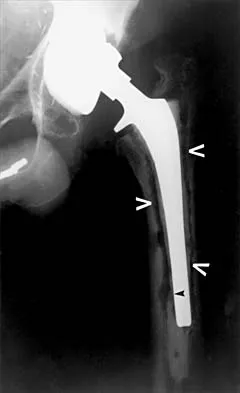

Figures 40a and 40b show the pre- and postoperative radiographs of an 82-year-old woman with bilateral hip pain who has had staged total hip arthroplasties. To minimize potential injury to the sciatic nerve at the time of surgery, the surgeon should

Explanation

To improve hip biomechanics and secure more suitable bone for acetabular fixation, the true acetabulum is often resurfaced in patients who have developmental dysplasia of the hip, thus lowering the hip center and lengthening the leg. Acute lengthening of more than 3 cm will place excessive tension on the sciatic nerve and require a femoral shortening to avoid sciatic nerve injury. The other maneuvers will not relieve sciatic nerve tension because of limb lengthening. Koval KJ (ed): Orthopaedic Knowledge Update 7. Rosemont, IL, American Academy of Orthopaedic Surgeons, 2002, pp 430-431.